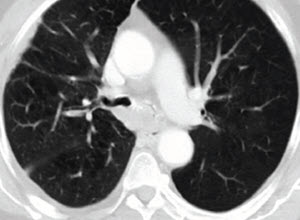

A 60-year-old woman with a large left hilar mass presented to the emergency room with worsening dyspnea. Advanced imaging demonstrated total occlusion of the left mainstem (LM) bronchus which was confirmed with direct visualization.